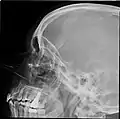

Lateral projection of the paranasal sinuses

Paranasal sinuses are a group of four paired air-filled spaces that surround the nasal cavity.[1] The maxillary sinuses are located under the eyes; the frontal sinuses are above the eyes; the ethmoidal sinuses are between the eyes and the sphenoidal sinuses are behind the eyes. The sinuses are named for the facial bones and sphenoid bone in which they are located. Their role is disputed and no function has been confirmed.